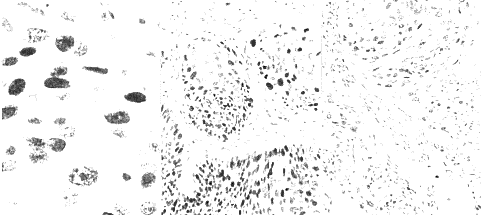

摘要 目的: 探讨子宫颈鳞癌中p21,p53的表达。方法: 应用免疫组织化学SP方法观察3例正常子宫颈组织、28例子宫颈慢性炎组织和45例子宫颈鳞癌组织中的增殖细胞核抗原(PCNA)、p21和p53的标记结果。结果: 3例正常子宫颈组织中3种均阴性;28例子宫颈炎p21、p53也均阴性,PCNA阳性率为2%。45例子宫颈鳞癌组织中,p21、p53和PCNA阳性率分别为16%、7%、98%。PCNA、p53阳性均定位于瘤细胞核,p21定位于细胞膜。p21,p53和PCNA阳性率与子宫颈鳞癌的病理分级无关(P>0.05);除PCNA(P<0.01)外,p21和p53与临床分期无明显关系(P>0.05)。结论: 检测p21,p53和PCNA有助于评估子宫颈癌的预后。